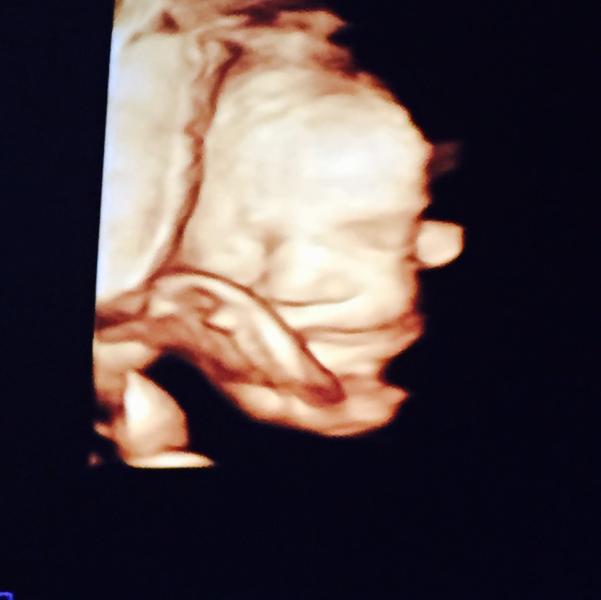

Вот моя девочка. Девочки, скиньте фотки УЗИ вашего 3 скрининга☺️

@jjjjjjk, моя тоже прятала лицо, мне пришлось чуть походить, чтоб она хотя бы чуть показала. Она резко поймала момент когда открыла